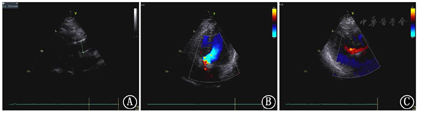

超声心动图所见:左房、左室稍大,升主动脉增宽,窦管连接部基本消失,主动脉根部右冠窦至无冠窦可见一纤细强回声光带,将主动脉根部分为两个腔,左冠状动脉起始部位置正常,内径约0.34cm,右冠状动脉起始部位于大动脉根部短轴约12~1点钟方位,似位于假腔,内径稍宽约0.48cm,升主动脉近端、主动脉根部及降部未见异常光带回声。室间隔与左室壁稍厚,室壁运动可,未见明显节段性室壁运动异常;CDFI示主动脉瓣中-重度反流,呈偏心性,沿二尖瓣前瓣走行。

超声提示:1、主动脉瓣中-重度关闭不全;2、主动脉窦部异常回声光带、右冠状动脉稍增宽(建议CTA除外主动脉窦部夹层累及右冠状动脉及主动脉瓣)(图4)。

经胸超声心动图虽然对心外结构显示价值有限,但能精细显示主动脉根部病变、主动脉瓣是否受累及瓣膜反流程度、冠状动脉是否受累及合并节段性室壁运动异常等心肌缺血表现,还能准确评估心脏的收缩和舒张功能[6]。此病例患者因其主动脉夹层累及部位特殊且局限,胸痛三联CTA漏诊,而经胸超声心动图对主动脉根部病变的显示优势帮助明确诊断并为临床及时正确处理提供依据。